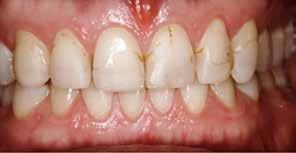

En 40 år gammel mand henvendte sig med bekymring for både æstetik og symptomer fra tænderne (Fig. 1). Han fortalte, at

Fig. 1. 40-årig sund og rask mand møder bekymret for sine slidte tænder. Klinisk ses frakturer og substanstab langs incisalkanterne på overkæbetænderne.

Fig. 1. A 40-year-old healthy man is concerned for his worn teeth. Clinically, fractures and loss of tooth substance are observed at the incisal edge of the upper front teeth.

han de seneste år havde mærket, at tænderne var blevet kortere og mere takkede, og han mærkede isninger ved indtagelse af kolde drikke. Han oplyste, at han i mange år havde drukket coca-cola dagligt, og at han skar tænder. Ellers var han sund og rask, og han havde normal salivaproduktion.

Klinisk undersøgelse viste et tandsæt med enkelte restaureringer, men med slitagedefekter okklusalt/incisalt på samtlige tænder fra 6’er til 6’er i over- og underkæbe (Fig. 2). Defekterne strakte sig tydeligt ind i dentinen. Baseret på anamnesen og de kliniske fund blev erosion set som hovedårsagen til tandsliddet, mens attrition formodedes at være en medvirkende faktor.